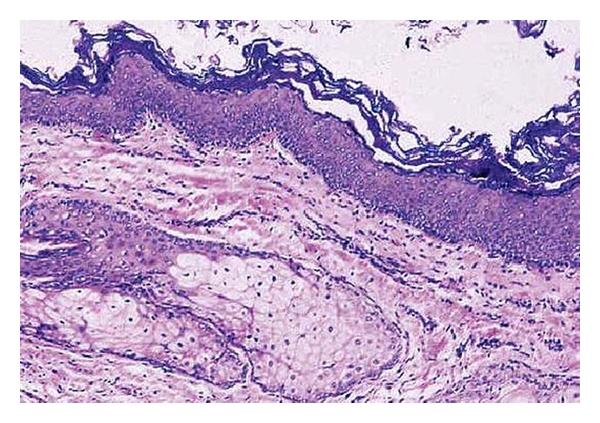

Dermoid cysts in the floor of the mouth may be congenital or acquired. The congenital form, according to the main theory, originates from embryonic cells of the 1st and 2nd branchial arch. The acquired form may be due to traumatic or iatrogenic causes and as a result of the occlusion of a sebaceous gland duct. Its occurrence is less and is estimated to be from 1.6 to 6.4% of the dermoid cysts of the body in adults and 0.29% of the head and neck tumors occurring in children. They may also be classified as anatomical and histological. Anatomically, they are divided into median genioglossal, median geniohyoid, and lateral cysts, while histologically they are divided into epidermoid, dermoid cysts and teratomas. Clinically, a distinction between supra and inferior type as well as between central and lateral type is proposed in relation to themylohyoidmuscle and themidline, respectively. Histologically, an estimation of dermoid, epidermoid, and teratoid cysts is reported. Enucleation via intraoral and/or extraoral approach is the method of treatment. Two case reports of dermoid cysts in the floor of the mouth are presented in this paper, and an evaluation with regard to pathology, clinical findings, differential diagnosis, and treatment is discussed.

口腔底部的皮样囊肿可能是先天性的或后天获得性的。根据主要理论,先天性皮样囊肿起源于第一和第二鳃弓的胚胎细胞。后天获得性皮样囊肿可能是由创伤或医源性原因引起的,也可能是皮脂腺导管阻塞的结果。其发生率较低,据估计,在成人体表皮样囊肿中占1.6%至6.4%,在儿童头颈部肿瘤中占0.29%。它们也可按解剖学和组织学进行分类。在解剖学上,它们分为正中颏舌肌型、正中颏舌骨型和外侧囊肿型,而在组织学上,它们分为表皮样囊肿、皮样囊肿和畸胎瘤。临床上,分别根据下颌舌骨肌和中线提出了上型和下型以及中央型和外侧型的区分。在组织学上,报告了皮样囊肿、表皮样囊肿和畸胎样囊肿的评估情况。通过口内和/或口外入路摘除是治疗方法。本文介绍了两例口腔底部皮样囊肿的病例报告,并讨论了病理学、临床发现、鉴别诊断和治疗方面的评估情况。